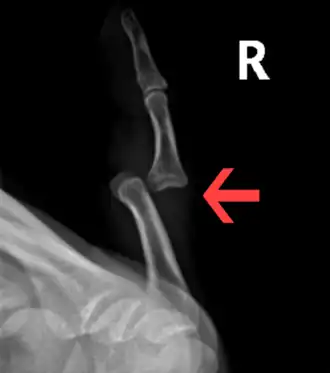

Radiograph of right fifth finger dislocation

Prognosis varies depending on the location and extent of the dislocation. The prognosis of a shoulder dislocation is dependent on various factors including age, strength, connective tissue health and severity of the injury causing the dislocation.[23] There is a good prognosis in simple elbow dislocations in younger people. Older people report more pain and stiffness on average.[23] Wrist dislocations are often difficult to manage due to the difficulty in healing the small bones in the wrist.[23] Finger displacement towards the back of the hand is often irreducible due to associated injuries, while finger displacement towards the palm of the hand is more readily reducible.[23] Overall, recovering from a joint dislocation can range from a few weeks to months, depending on the severity of the injury.[4]

• Finger

• Interphalangeal (IP) or metacarpophalangeal (MCP) joint dislocations[41]

• In the United States, men are most likely to sustain a finger dislocation with an incidence rate of 17.8 per 100,000 person-years.[42] Women have an incidence rate of 4.65 per 100,000 person-years.[42] The average age group that sustain a finger dislocation are between 15 and 19 years old.[42]

• The most common dislocations are in the proximal interphalangeal (PIP) joints.[8]